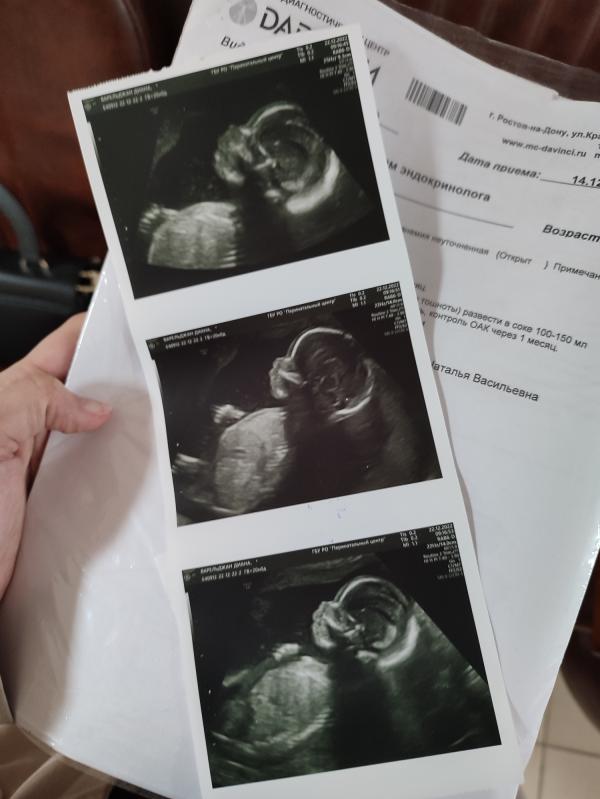

Сегодня был второй скрининг) ну что там за чудо такое🥰 хоть уже сейчас фото в рамочку и на стену)

С порога сказала врачу, чтобы не говорил мне пол вслух) так она мне в конце приема на бумажке пол написала и степлером скрепила, чтобы я не заглядывала)) теперь передам конверт кондитеру и утро 31 декабря будем отмечать в семейном кругу с цветным тортиком)

Сегодня утром мы порезали торт) кто говорил, что вы видите девочку, как вы это делаете?)) у нас действительно, в мае будет дочь🥰